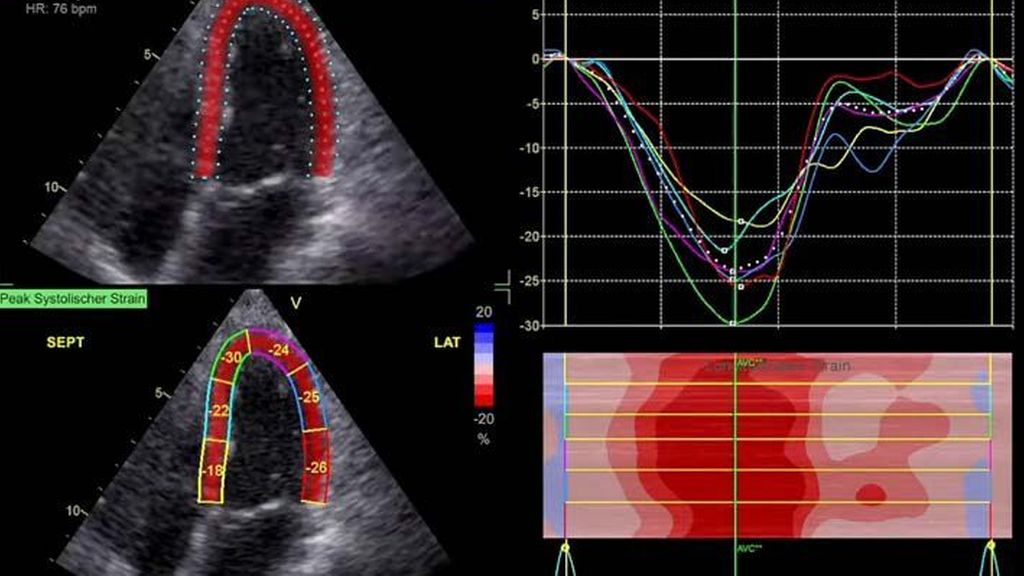

Im Echolabor des Pyhrn-Eisenwurzen Klinikums Steyr wird jede Form der Myokardwandverdickung mittels einer vollständigen Standardechokardiografie untersucht.2 Dabei wird auch ein Fokus auf die kontrastmittelunterstützte Sonografie gelegt, um die tatsächliche Dicke des Myokards zu vermessen.3 Die Verdickung sollte optimalerweise mittels 3D-LV-Massenmessung erfolgen. Die Messung im 2D-Bild ist dahingehend unterlegen. Ebenso wird jede Myokardwandverdickung mittels 2D-„strain imaging“ in der transthorakalen Echokardiografie (TTE) untersucht.4–6 Der „strain“ ist eine Messung der longitudinalen Funktion des Herzens (Video 1).

Der erste Fall beschäftigt sich mit einem Patienten mit einer hypertrophen Kardiomyopathie (HCMP). Er gibt eine deutliche Belastungsdyspnoe sowie einen ausgeprägten Leistungsknick an. Es wurde infolgedessen eine Untersuchung mittels standardisierter Echokardiografie inklusive „strain imaging“ durchgeführt. Der globale longitudinale „strain“ (GLS) mit –16% in Ruhe war gering reduziert. Es konnte kein relevanter LVOT-Gradient in Ruhe nachgewiesen werden. In der Belastungssituation (Handgrip, Valsalva, Kniebeugen und als Vorbereitung zur Untersuchung ein ausgiebiges Frühstück und Kaffee sowie ein am Vorabend konsumiertes Bier) konnte bei Kniebeugen mit einer Herzfrequenz von 126/min ein Spitzengradient bis 52mmHg dargestellt werden. Somit ergibt sich die Diagnose einer HOCMP mit einem belastungsinduzierten Gradienten. Bei bereits bestehender und ausgereizter Therapie unter Betablocker besteht die Indikation zur Therapie mittels des kardialen Myosininhibitors Mavacamten (Klasse-IIa-Empfehlung laut ESC).1 Darunter verbesserte sich die klinische Situation des Patienten deutlich, der Patient konnte uneingeschränkt Sport ausüben. Über die Zeit kam es zu einer geringen Reduktion der LV-Masse und einer geringen Zunahme des LV-„strain“. Die Belastungssituation zeigte durchwegs normale „strain“-Werte mit –20% (mit regionaler Reduktion bei Myokardwandverdickung im Sinne einer Hypertrophie). Die myokardiale Arbeit beim konkreten Patientenfall ist ebenso in Ruhe im grenzwertigen und unter Belastung im guten Normalbereich.6,8,9 Der Patient ist derzeit unter 5mg Mavacamten einmal täglich optimal eingestellt. Die EF in Ruhe ist konstant bei 50–55%. In Video 2 werden unterschiedliche Gradienten dargestellt, um eine HOCMP mit LVOTO von z.B. einer Mitralklappeninsuffizienz zu unterscheiden.Die Verdachtsdiagnose wurde mithilfe der Echokardiografie gestellt und durch das septal betonte „patchy“ LGE im MRT bestätigt.1,5

Die Paradedisziplin, die den „strain“ als Untersuchung in aller Munde gebracht hat, ist die Diagnostik der Amyloidose. Typisch (aber nicht pathognomonisch) ist dabei das „apical sparing“. In Video 3 ist ein Patient mit einer typischen ATTR-Amyloidose im „bullseye display“ des „strain“ im 17-Segmentmodell des LV zu sehen. Ebenso werden andere Zeichen in der Echokardiografie der Amyloidose präsentiert. Im konkreten Fall wurde die Sinnhaftigkeit, fast Notwendigkeit, der atrialen Bildgebung besprochen. Das Vollbild der Amyloidose zeigt eine deutliche Myokardwandverdickung des LV, in der frühen Phase kann diese jedoch noch fehlen. Als erstes Zeichen kann eine Veränderung des „strain“, insbesondere das linke Atrium (LA) betreffend, vorliegen.10 Somit ist in Summe festzuhalten, dass die Messung der longitudinalen Funktion des linken Atriums für eine Früherkennung erhöhter Füllungsdrücke dienlich sein kann, analog dem HbA1c für erhöhte Füllungsdrücke. Besonders bei einem LA-„strain“ in der Reservoirphase von unter 20% sollte man das Vorliegen einer möglichen beginnenden Form einer restriktiven Kardiomyopathie in Erwägung ziehen.1,10 Im MRT sind deutlich verlängerte T1-Zeiten ein Hinweis für das Vorliegen einer Amyloidose(neben dem generalisierten kreisrunden LGE (abhängig von der Aufzeichnungsphase und der Messung des erhöhten Extrazellulärvolumens).1

Andere Formen der Myokardwandverdickung, die mit „strain“ und MRT gut dargestellt werden können, sind einerseits die Differenzierung der Auswirkung der arteriellen Hypertonie (weiblich, 72a) bei Vorliegen einer Herzinsuffizienz mit normaler EF, einem GLS von –15,4%, einem LA-„strain“, in Reservoirphase 25% bei gering verlängerten T1-Zeiten im MRT. Andererseits kann Steroidabusus (männlich, 44a) zu einem reduzierten „strain“ mit gering verlängerten T1-Zeiten und einer Normalisierung der bildgebenden Befunde nach 2 Jahren nach Absetzen führen bzw. eine Mitochondriopathie (männlich, 32a) zu einer unklaren Myokardverdickung mit diffus reduziertem „strain“ und reduzierter LV-Funktion.4,11,12